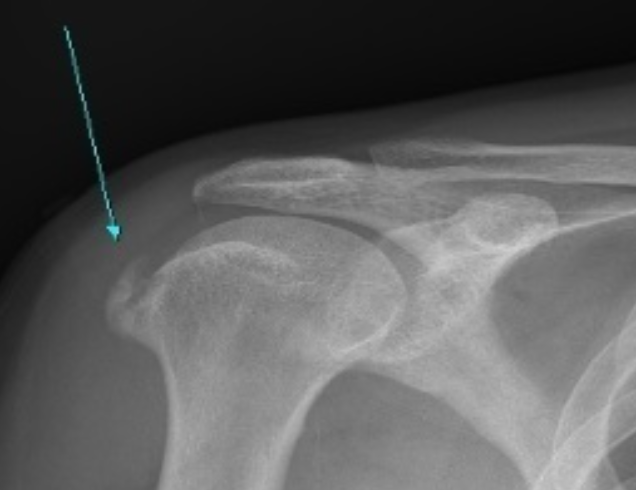

- 예고없이 찾아오는 격렬한 통증! 형성기 석회가 침착되는 시기로 통증을 비롯한 다른 증상은 거의 없습니다.

용해기 몸에서 석회를 없애기 위해서 석회 주위로 혈관을 만들어 내는 시기로 활발한 염증 반응이 일어나면서 통증이 생깁니다.